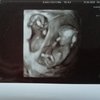

A więc przedstawiam Wam moje cuda i moje ulubione zdjęcie :-)

Zdjęcie bardzo fajne. A Maluszki przeslodkie

Sliczne malutkie skarbeczki, aż serce rośnie od takich zdjęć.A więc przedstawiam Wam moje cuda i moje ulubione zdjęcie :-)